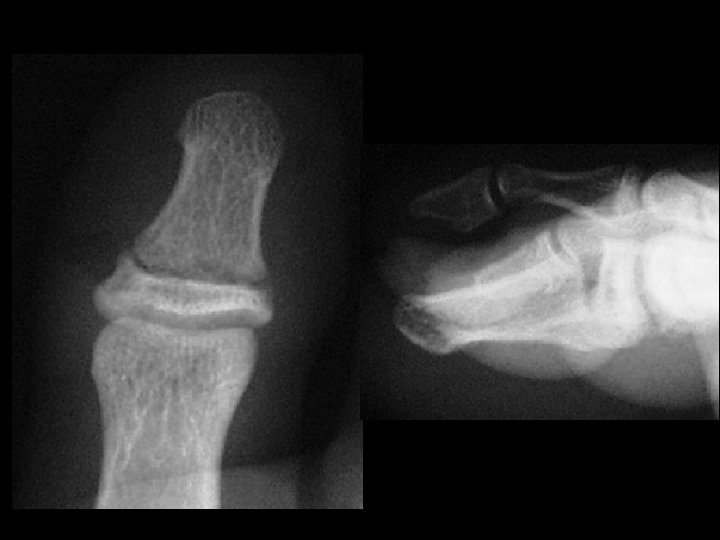

Nail bed injury • Findings: – Horizontal fracture at the base of the great toe distal phalanx – Consider this as an open fracture with a high incidence of osteomyelitis • ddx: – NONE! – This is an Aunt Minnie!

Gout • Findings: – Large erosions with overhanging margins at the great toe MTP joint – Dense periarticular swelling – Sparing of the joint space • ddx: – NONE! – This is an Aunt Minnie!